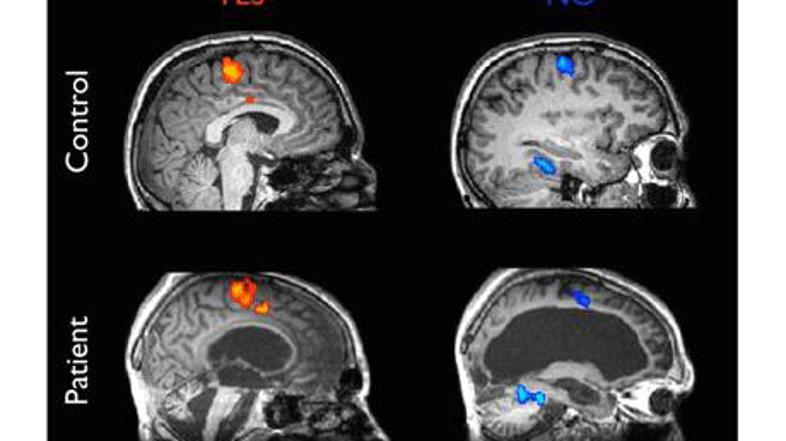

29-letniku so se ob misli na različne odgovore aktivirali različni predeli možga Žurnal24 main

Znanstveniki so odkrili, da se lahko pogovarjajo z njim prek nadzora možganske aktivnosti. S funkcijsko magnetno resonanco so merili odziv možganov na preprosta vprašanja. Ker so možganski signali, povezani z da in ne, preveč podobni, so mu namesto tega predlagali, naj za 'da' razmišlja o igranju tenisa, za 'ne' pa o sprehajanju okoli hiše. Te misli sprožijo dejavnost v različnih možganskih centrih.